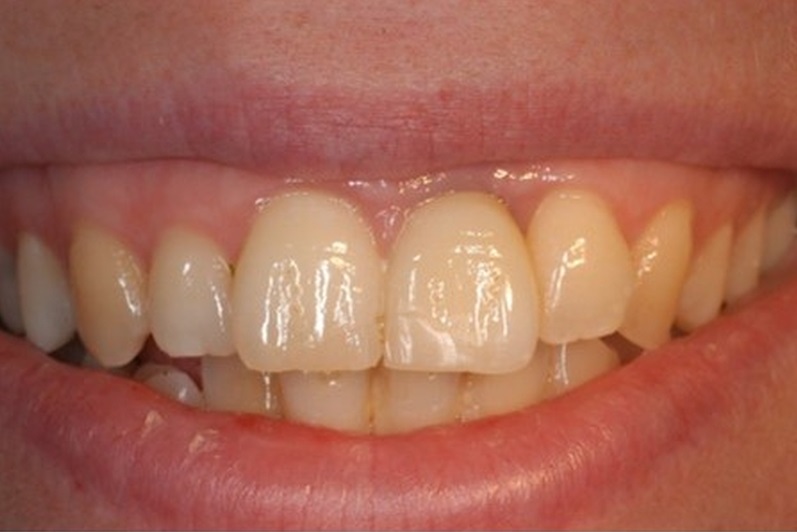

02/12 - Extraction of tooth 21 after endodontic treatmentTreatment of dehiscence defect with cerabone® & Jason® membrane - Dr. M. Steigmann